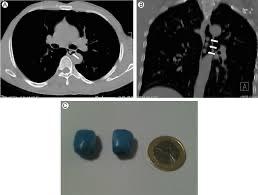

On-site hands on Bronchoscopy Training

Hands-on Training of Bronchoscopy/ Fellowship in Pediatric Pulmonology@Respiratory Foundation of India

After the completion of 12 weeks online classes,twice in a week, we provide Hand-on Training…